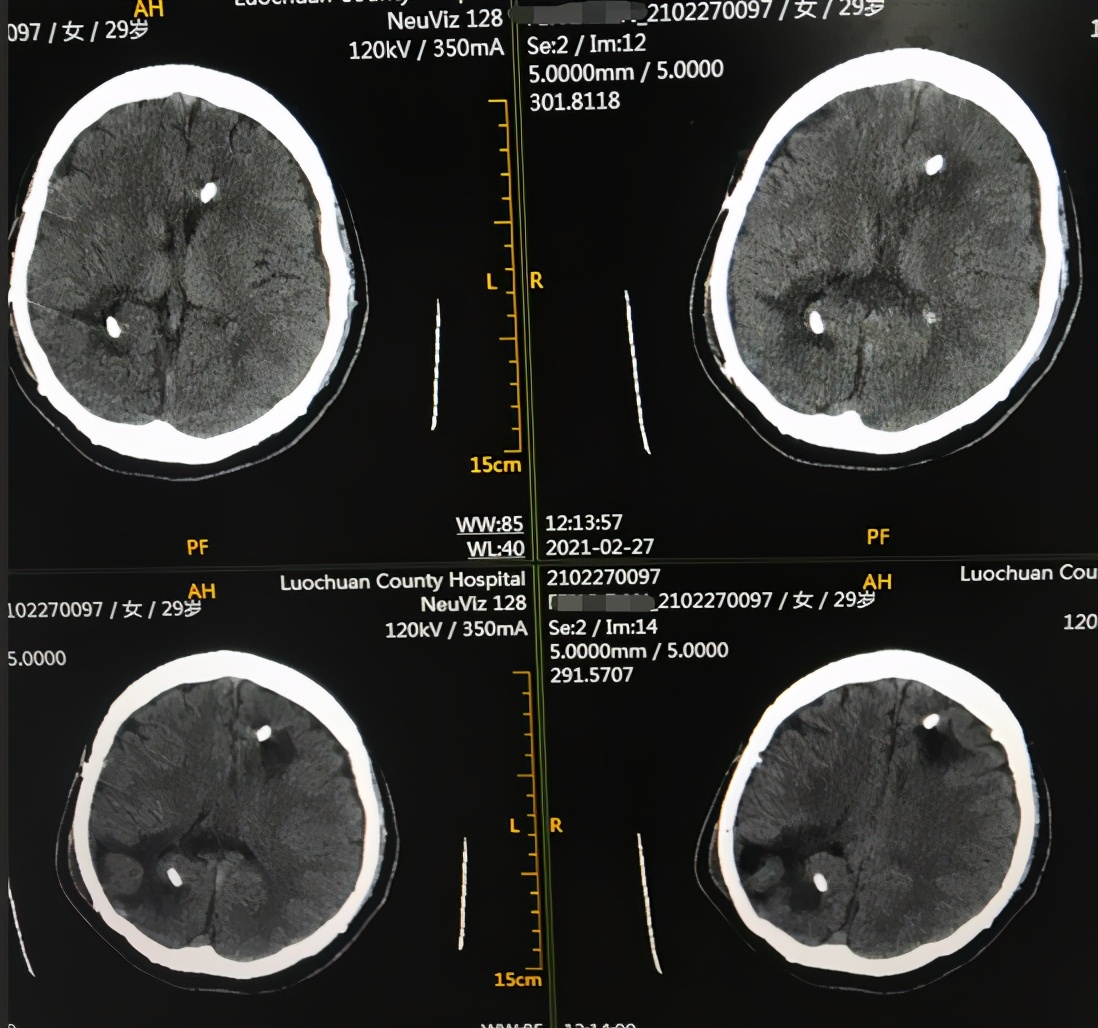

出院后111天即2021年2月27日,家属欢喜地发来视频:言语交流变正常,身体不断变好本人心情也常常很愉悦,时常自己唱歌( 图-42 ),当地医院查头颅CT未见异常( 图-43 )。

图-43: 2021年2月27日头颅CT